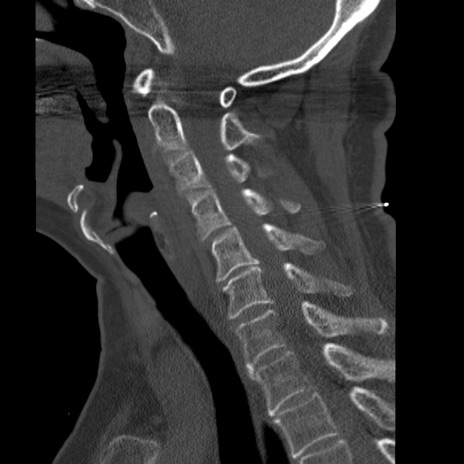

症例50 頚椎CT(矢状断像)

頚椎CT